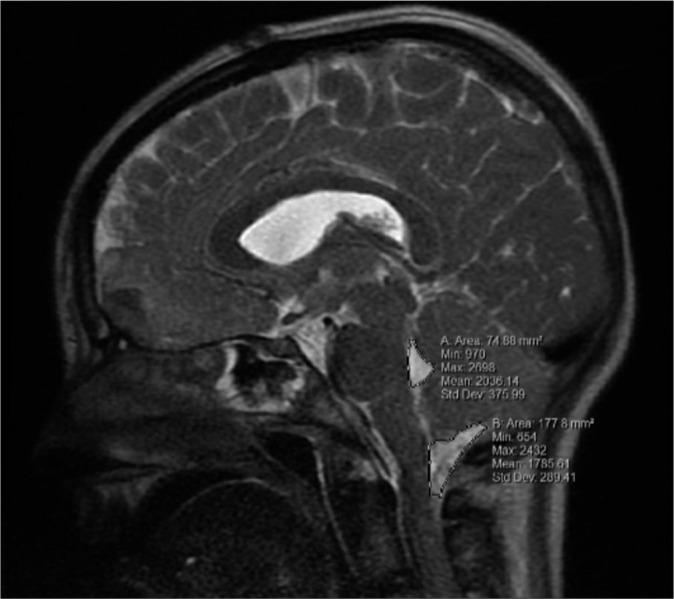

METHODS

This is a retrospective chart review over 11 years across two medical centers. Patients included were under 18 years who presented with a cerebellar contusion. Patients were stratified within the study group based on discharge Glasgow outcome scale (GOS) and reviewed for prognostic factors contributing to outcome. Mid sagittal area of the 4 ventricle and cisterna magna were measured using magnetic resonance imaging and compared within the groups.

方法

这是一项对两个医疗中心11年间病例的回顾性研究。纳入的患者为18岁以下的小脑挫伤患者。根据出院时的格拉斯哥预后量表(GOS)对研究组患者进行分层,并对影响预后的因素进行分析。使用磁共振成像测量第四脑室和小脑延髓池的矢状面中部面积,并在各组之间进行比较。